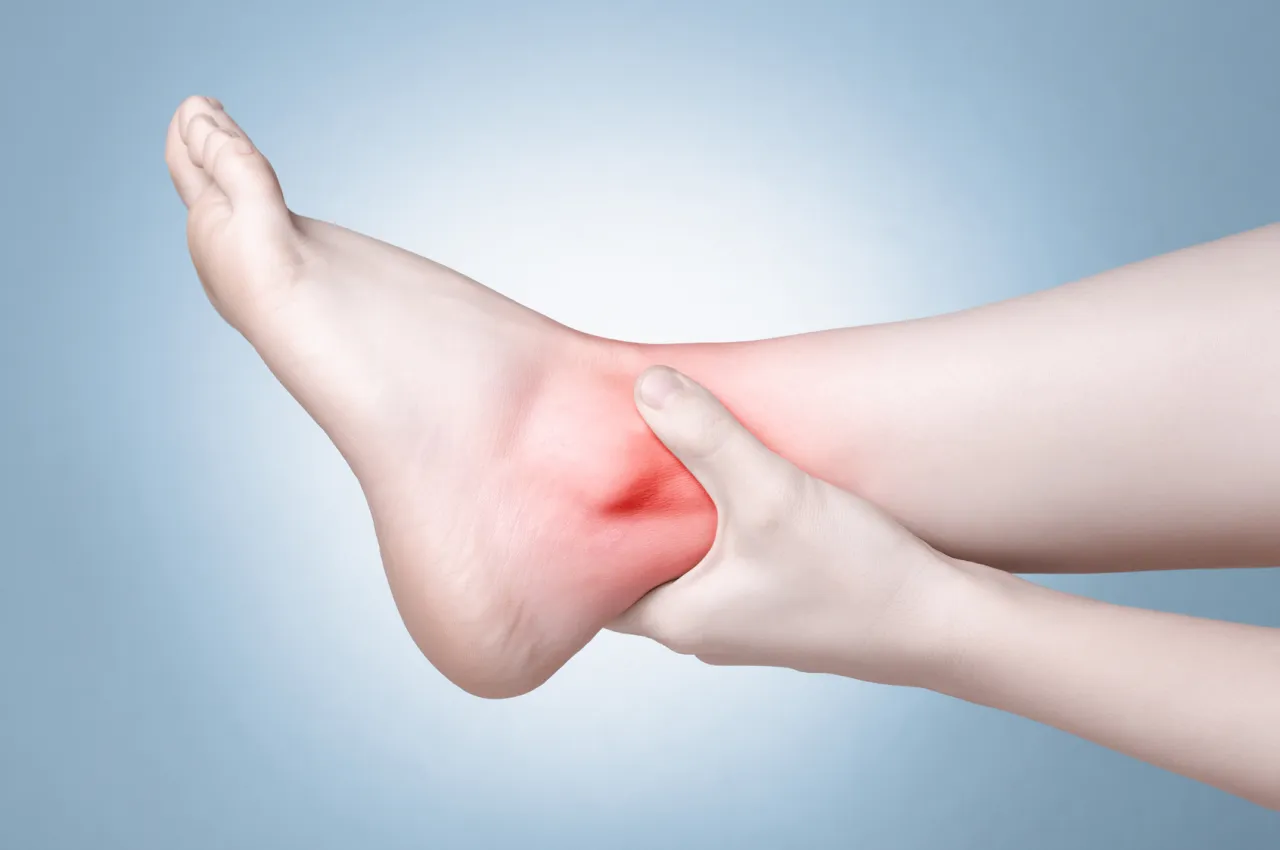

Objawy skręcenia obejmują ból, obrzęk oraz siniaki w okolicy uszkodzonego stawu. Osoba z tym urazem może również odczuwać ograniczenie ruchomości, co utrudnia normalne funkcjonowanie. Skręcenie najczęściej występuje w stawach skokowych, kolanowych oraz nadgarstkowych, gdzie więzadła są szczególnie narażone na uszkodzenia podczas nagłych ruchów lub upadków.

Potencjalne zagrożenia związane ze skręceniem obejmują przewlekły ból oraz osłabienie stawu, co może prowadzić do częstszych urazów w przyszłości. Jeśli skręcenie nie jest odpowiednio leczone, może dojść do powikłań, takich jak uszkodzenie więzadeł lub powstawanie blizn, które ograniczają ruchomość stawu. Dlatego ważne jest, aby nie ignorować objawów skręcenia i skonsultować się z lekarzem w celu oceny stanu zdrowia.

Aby rozpoznać poważne skręcenie, należy zwrócić uwagę na objawy, takie jak intensywny ból, który utrzymuje się i nie ustępuje po odpoczynku. Jeśli obrzęk wokół stawu jest znaczny, a ruchomość jest znacznie ograniczona, może to wskazywać na poważniejsze uszkodzenie. W takich przypadkach warto skonsultować się z lekarzem, aby ocenić stan i uniknąć dalszych komplikacji.

Poważne skręcenia mogą prowadzić do długoterminowych konsekwencji, takich jak przewlekły ból lub osłabienie stawu. Nieleczone skręcenia mogą prowadzić do uszkodzenia więzadeł, co zwiększa ryzyko wystąpienia kolejnych urazów w przyszłości. Dlatego ważne jest, aby nie lekceważyć objawów i szukać pomocy medycznej, jeśli ból i obrzęk nie ustępują.